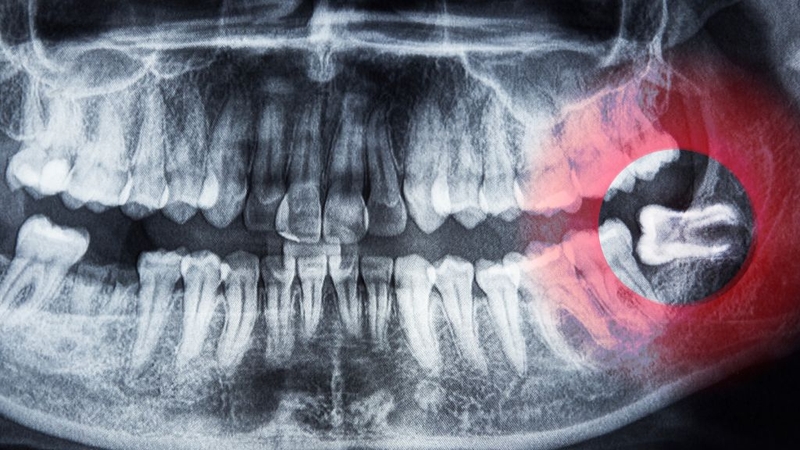

Mọc sai hướng

Một trong những lý do phổ biến khiến răng khôn cần được nhổ bỏ là tình trạng mọc sai hướng. Do cung hàm không còn đủ khoảng trống, răng khôn thường mọc lệch sang răng số 7 hoặc mọc ngầm dưới nướu. Khi mọc như vậy, răng khôn có thể gây chèn ép, tạo áp lực lên răng bên cạnh, làm bệnh nhân cảm thấy đau nhức và khó chịu kéo dài.

Nhổ răng khôn khi chúng mọc sai hướng

Nếu để lâu, răng khôn mọc sai hướng không chỉ làm hỏng cấu trúc của răng kế cận mà còn có thể gây viêm lợi, hình thành túi mủ hoặc khiến toàn bộ hàm răng bị xô lệch. Trong nhiều trường hợp, tình trạng này còn làm suy giảm khả năng ăn nhai, ảnh hưởng đến chất lượng cuộc sống hằng ngày. Vì vậy, việc nhổ bỏ răng khôn mọc lệch thường được coi là giải pháp cần thiết để tránh biến chứng nghiêm trọng hơn.